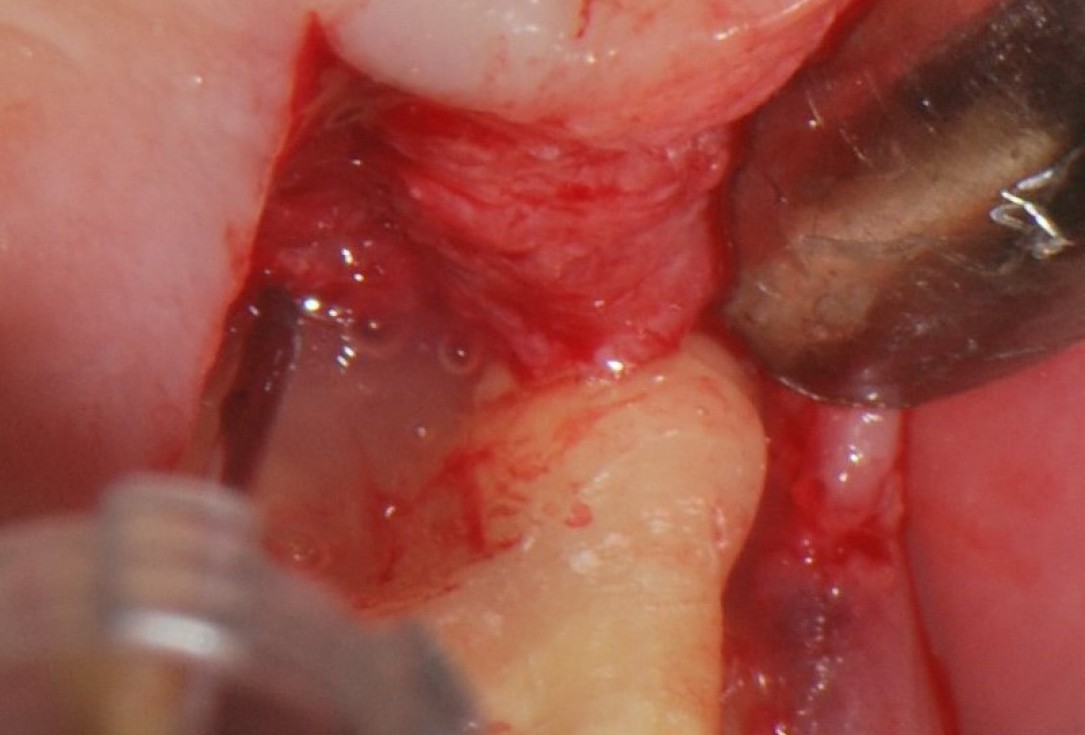

04/06 - Flap elevation by a midcrestal incision and application of Straumann® Emdogain® to the defect site.

Treatment of a periodontal bone defect adjacent to an edentulous site using Straumann® Emdogain® - Prof. Dr. P. Windisch